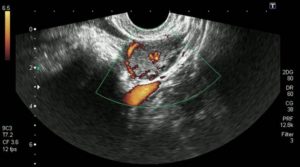

Лютеиновая железа, как и любой другой орган в нашем теле имеет свои собственные характеристики, которые присущи именно ему и позволяют отличить искомый орган от других. Тогда первый вопрос, который возникает — как выглядит желтое тело на УЗИ? Оно представляет собой мягкое шарообразное, слегка вытянутое образование, которое находится непосредственно рядом с яичником.

Желтое тело на УЗИ фото

На УЗИ желтое тело определяется как округлое неоднородное образование.

Его видно и при методике исследования через брюшную стенку (трансабдоминальная методика УЗИ), но более достоверные результаты диагностики получают при трансвагинальном методе с использованием внутривагинального датчика.

На экране аппарата УЗИ желтое тело выглядит как небольшой мешок, расположенный вблизи яичника. Врач проводит необходимые замеры и заносит их в заключение.